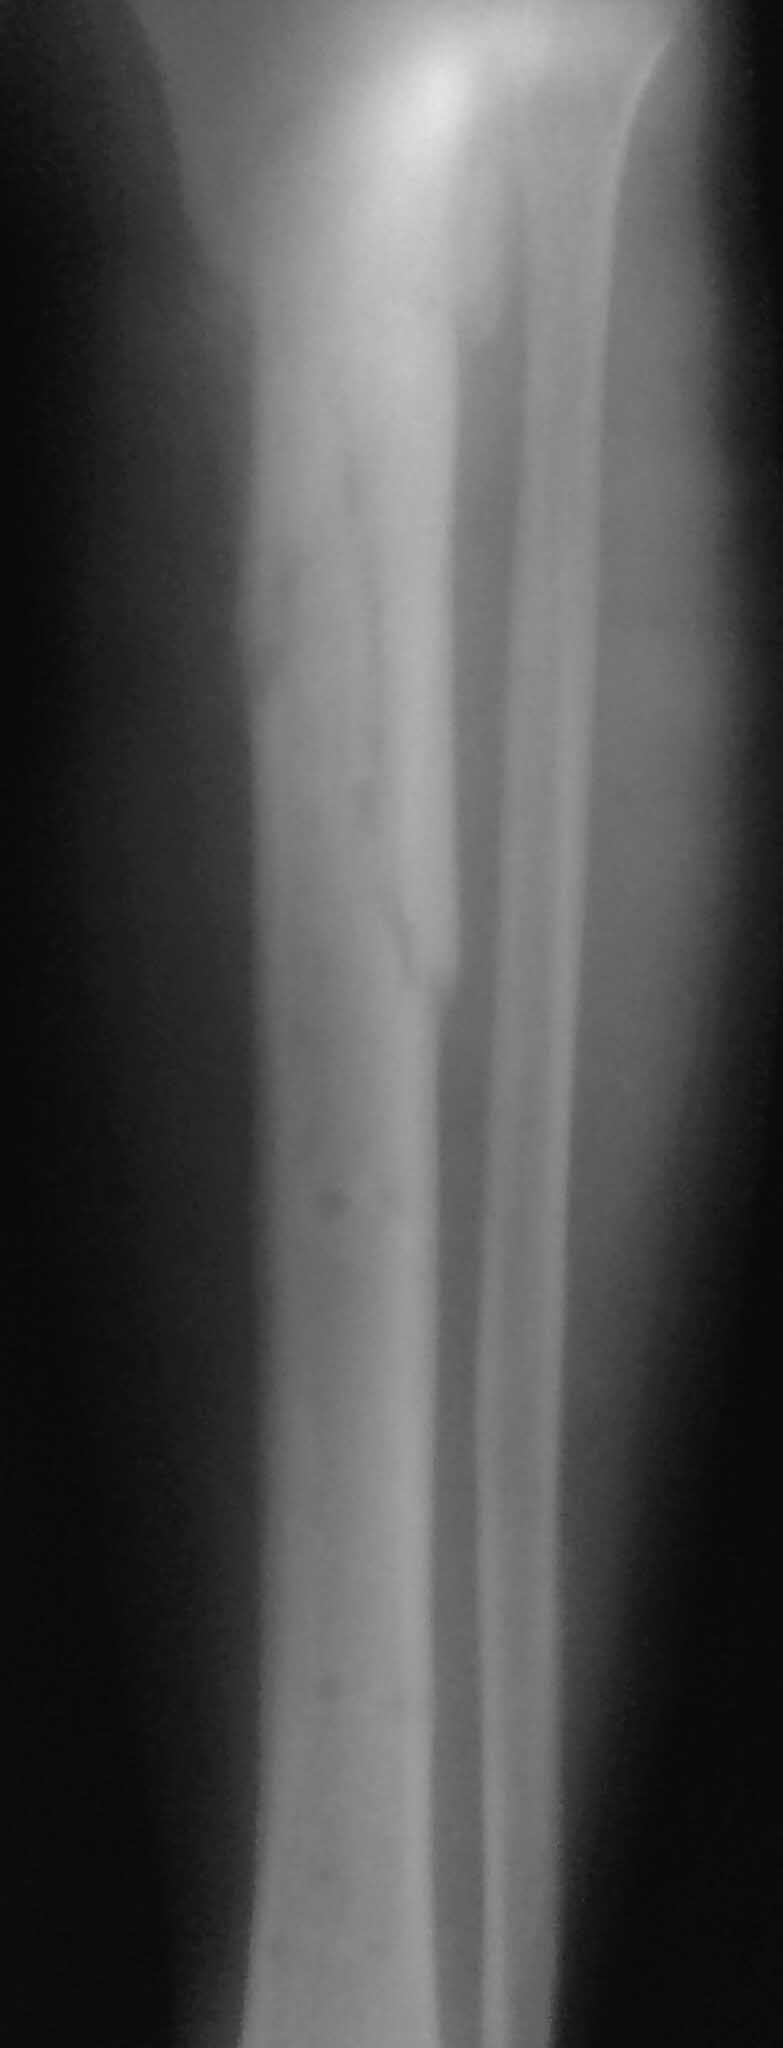

Спасибо за обсуждение.Отправил остальные R, изиняюсь за качество.

3.Перелом на 2 уровнях, есть искривление костно-мозгового канала. Проксимальный отломок короткий.

На мой взгляд не стоит переходить к погружным методикам. Повторите внеочаговую фиксацию по Илизарову - дистракционно-компрессионный остеосинтез. Проведите остеотомию малоберцовой кости. В проксимальном отломке следует более тщательно, классически провести спицы: 2 на 1,5 см ниже суставной щели с перекрестом 90, дополнительно проведите 1 спицу на консольных приставках снутри кнаружи во фронтальной плоскости с упором, тотчас над верхушкой промежуточного отломка. 2 кольцо следует расположить под концом проксимального отломка, в нем в дальнейшем провести спицу с упором снаружи кнутри во фронтальной плоскости. До проведения спицы в среднем кольце следует смонтировать аппарат в виде трубы, 3 кольцо с 2 спицами расположить над лодыжками. После компоновки аппарата и натяжения спиц в крайних кольцах следует дать одномоментную дистракцию до напряжения аппарата. Затем следует провести встречно-боковую компрессию спицами на уровне проксимального перелома. Спицы используйте не менее 1,8 мм. В дальнейшем проводите дистракцию по 0,5 - 1 мм в сутки 10-14 дней с целью формирования межотломкового регенерата. Вся "интерпозиция" перестроится в остеогенную ткань. Затем верните аппарат в нейтральное положение (сбросьте дистракцию и убедитесь, что есть встречно-боковая компрессия или повторите ее. Уверен, что через 3 месяца консолидация завершится.